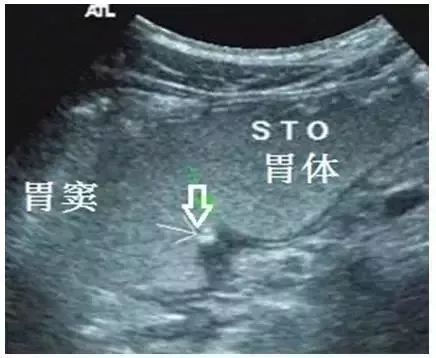

图4 胃窦部前壁溃疡

(活动期,A横切面,B纵切面)